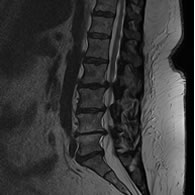

• Resonancia Magnética de columna lumbar, permite evaluar las deformidades del saco dural, así como la presencia de discopatias y la permeabilidad de los forámenes de conjunción.